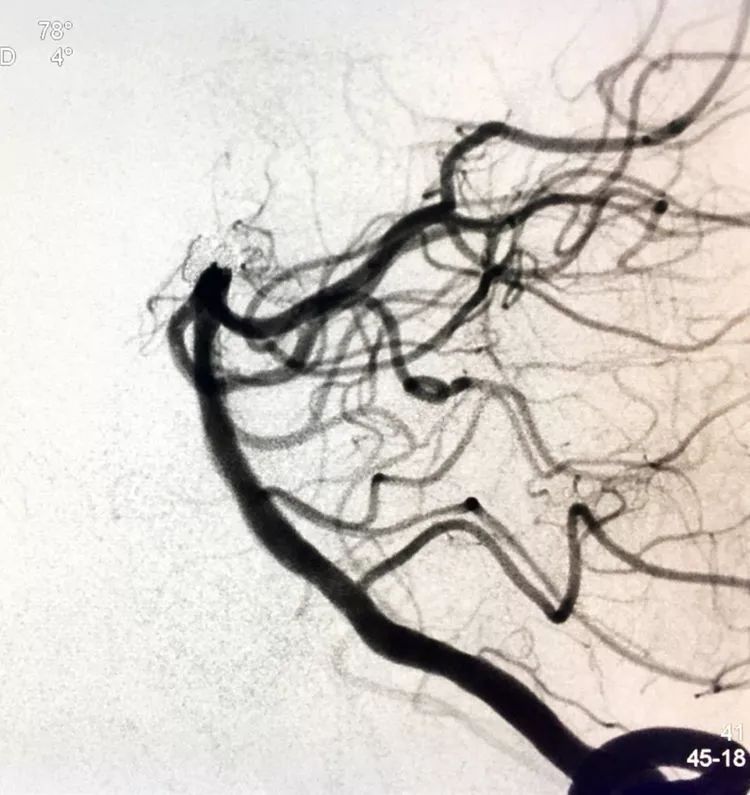

回到工作位造影,显示基底动脉顶端动脉瘤完全栓塞,基底动脉顶端四根血管畅通。

术后左椎动脉正位、侧位的造影和蒙片